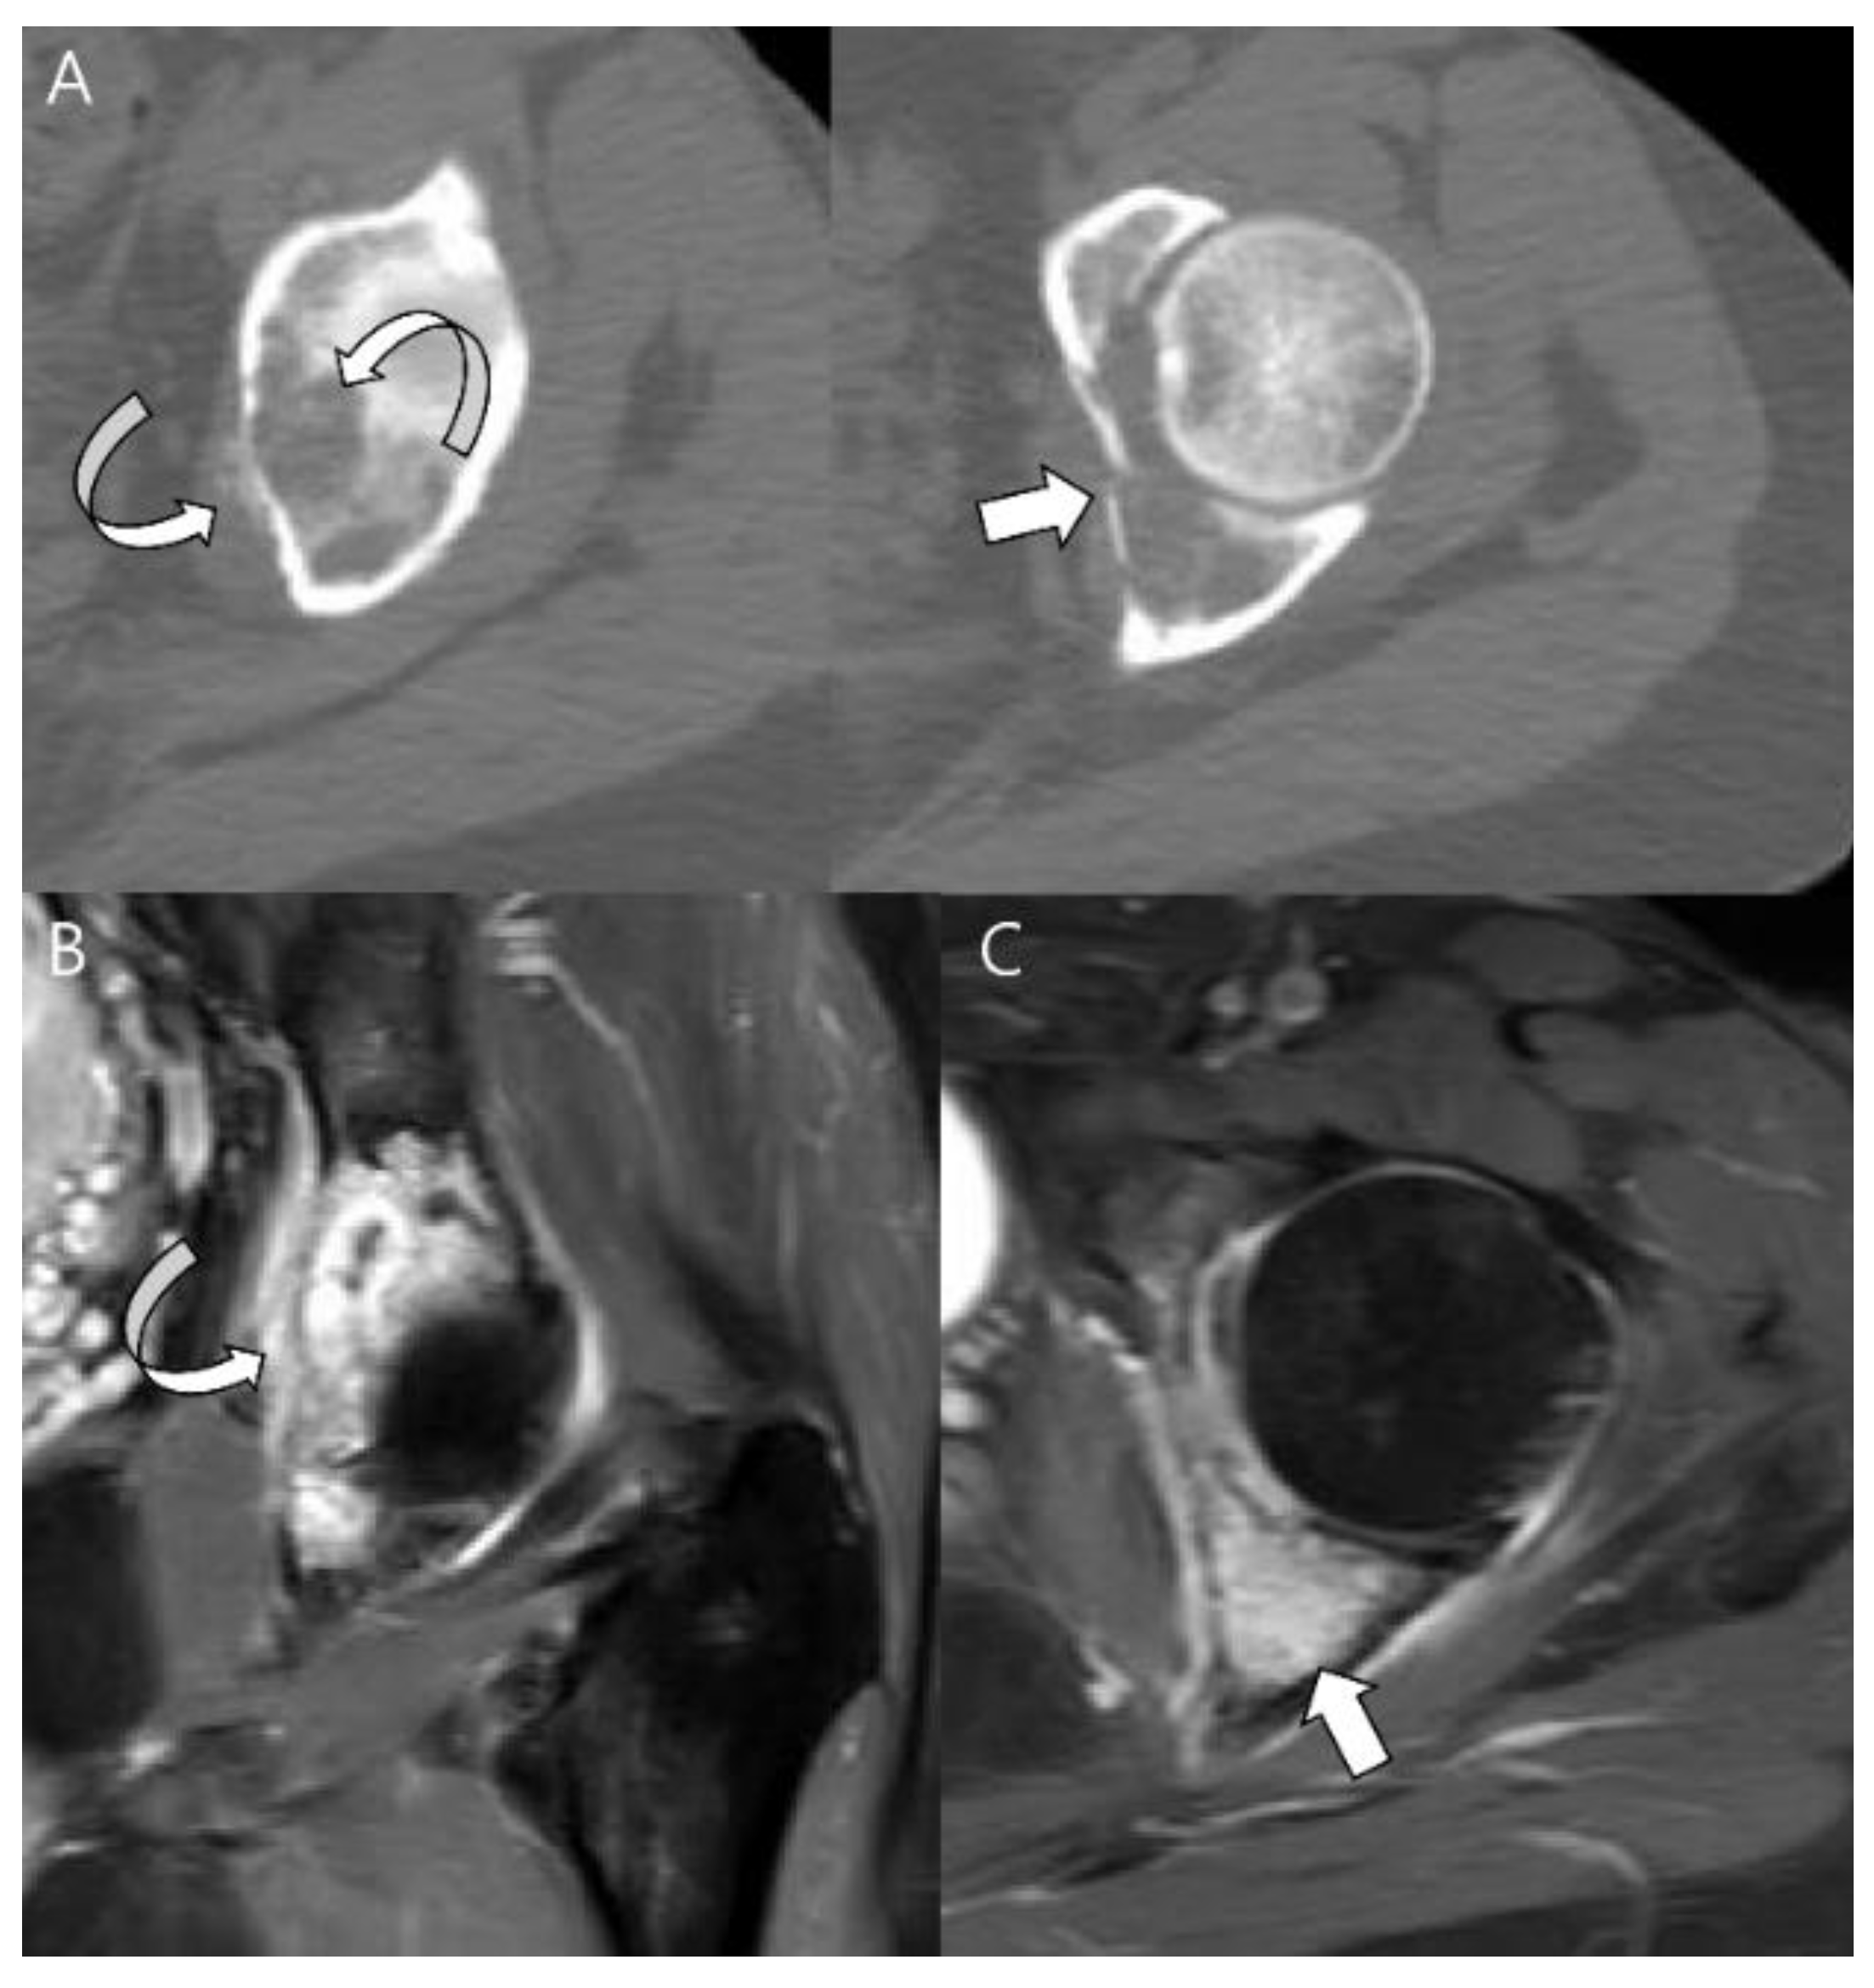

- Collins, M.S.; Koyama, T.; Swee, R.G.; Inwards, C.Y. Clear cell chondrosarcoma: Radiographic, computed tomographic, and magnetic resonance findings in 34 patients with pathologic correlation. Skelet. Radiol. 2003, 32, 687–694. [Google Scholar] [CrossRef]

- Kumar, R.; David, R.; Cierney, G., 3rd. Clear cell chondrosarcoma. Radiology 1985, 154, 45–48. [Google Scholar] [CrossRef]

- Bagley, L.; Kneeland, J.B.; Dalinka, M.K.; Bullough, P.; Brooks, J. Unusual behavior of clear cell chondrosarcoma. Skelet. Radiol. 1993, 22, 279–282. [Google Scholar] [CrossRef]

- PPresent, D.; Bacchini, P.; Pignatti, G.; Picci, P.; Bertoni, F.; Campanacci, M. Clear cell chondrosarcoma of bone. Skelet. Radiol. 1991, 20, 187–191. [Google Scholar] [CrossRef] [PubMed]